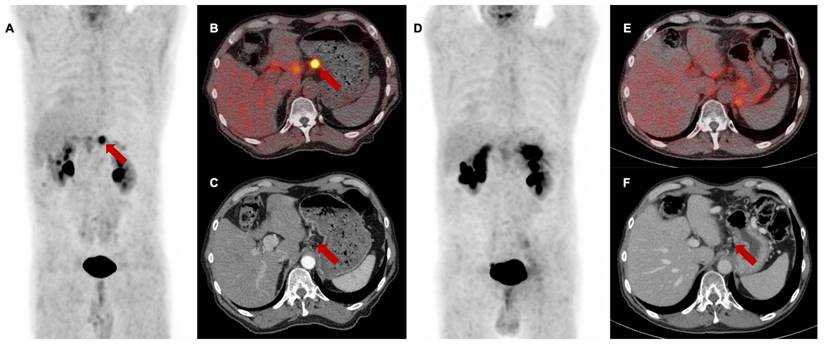

Baseline [68Ga]Ga-FAPI-46 PET/CT of a patient with locally recurrent pancreatic adenocarcinoma at the mesentery root. A maximum intensity projection with a red line representing axial slices B-E, B and D transaxial fusion of PET/CT data of the upper abdomen, C and E transaxial, corresponding contrast-enhanced CT scan in arterial phase. Suspicious peripancreatic lymph nodes with a short axis diameter over 10 mm (red arrows) without FAPI signal were rated benign and consequently downstaged.

N staging at baseline

Regarding N stage, FAPI-PET led to a downstaging of morphologically suspicious peripancreatic and mesenteric lymph nodes from N1 or N2 to N0 in 12 of 27 cases (44%). In eight cases (30%), these findings resulted in a change of the target volume as these lymph nodes were not included in the irradiation field. This N downstaging by [68Ga]Ga-FAPI-46 PET/CT was confirmed by stable absence of increasing lymph node diameters during follow-up and by the lacking evidence for tumor progression within the clinical assessment of patients after radiotherapy every three months (example given in Figure 2).